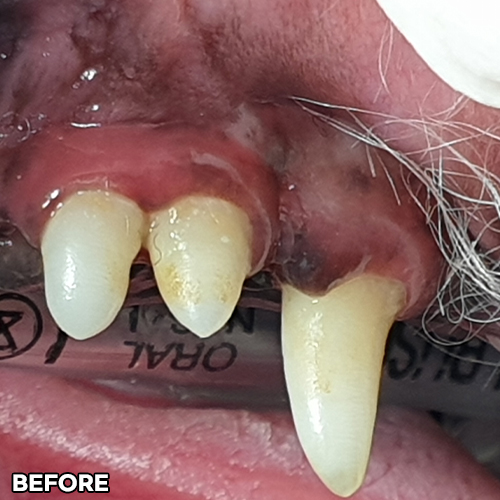

[심한 치주염 치료 후 2주 경과]